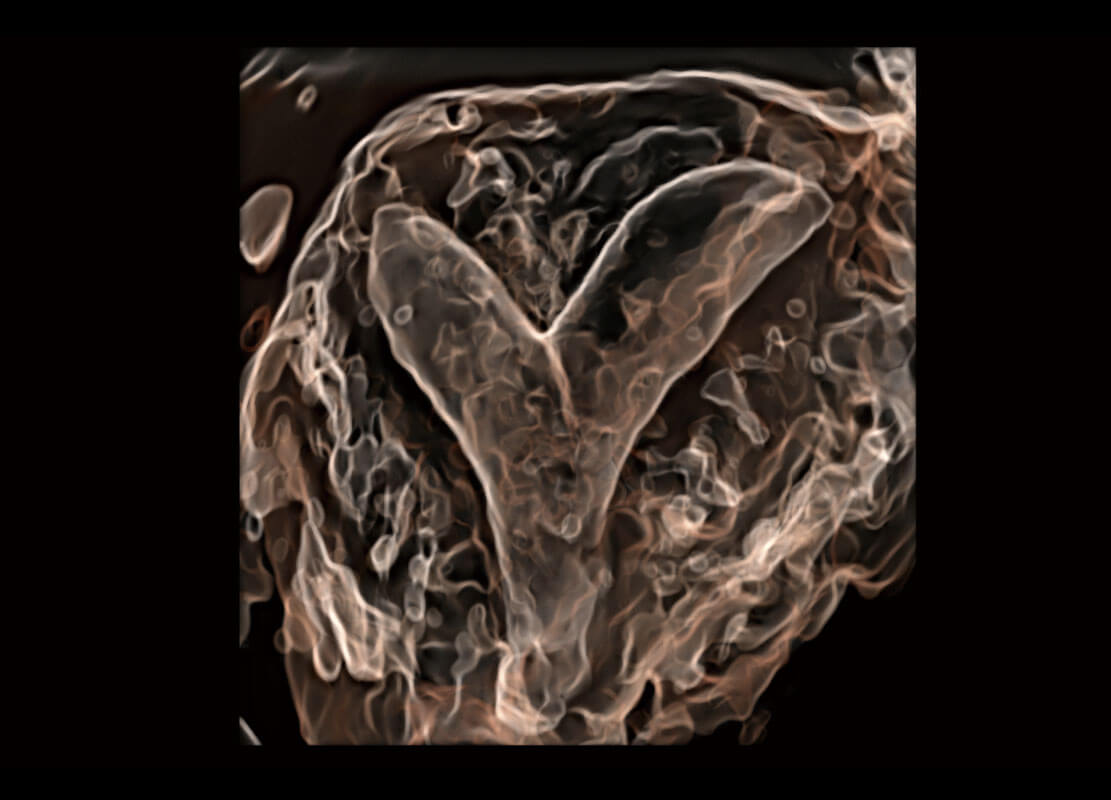

P60搭载一系列胎儿心脏成像技术,实现精细的胎儿心脏评估。

四腔切面

四腔心血流

右室双出口

胎心容积成像